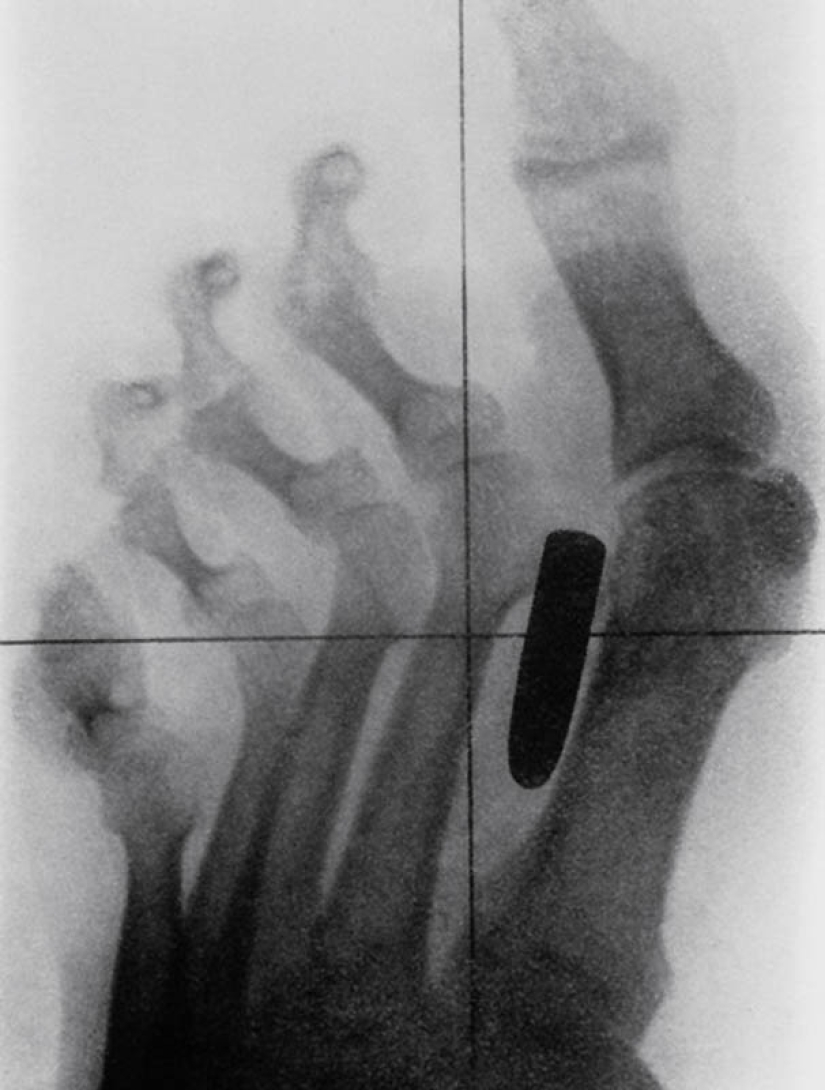

4. Uña en los huesos de los dedos índice y medio de un macho adulto.